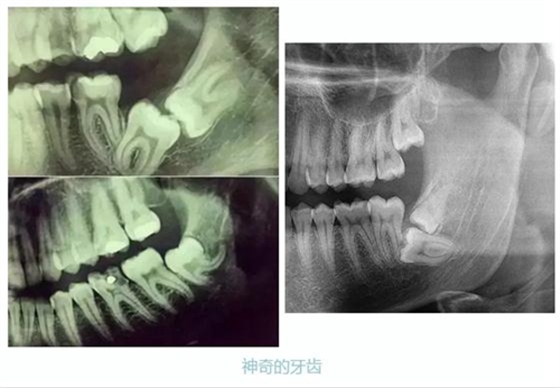

先放幾張圖,讓你們漲漲姿勢,不拍片根本不知道你的牙齒長得會有多奇葩!

從上圖中可以知道除了外層的一點(diǎn)牙釉質(zhì),牙齒里面出了問題,肉眼是無法觀察到的。牙醫(yī)不長透視眼當(dāng)然不能透過現(xiàn)象看到牙齒本質(zhì)嘍。因此,為了對牙齒進(jìn)行全面的了解,拍個(gè)牙片還是很有必要的。